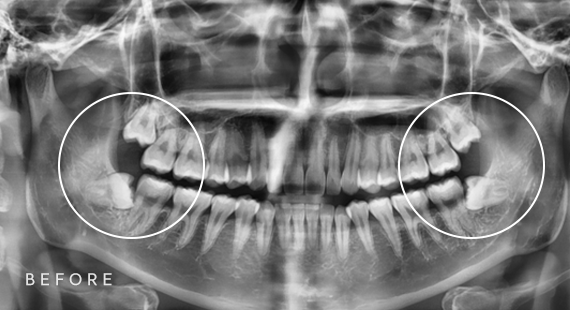

사랑니 발치